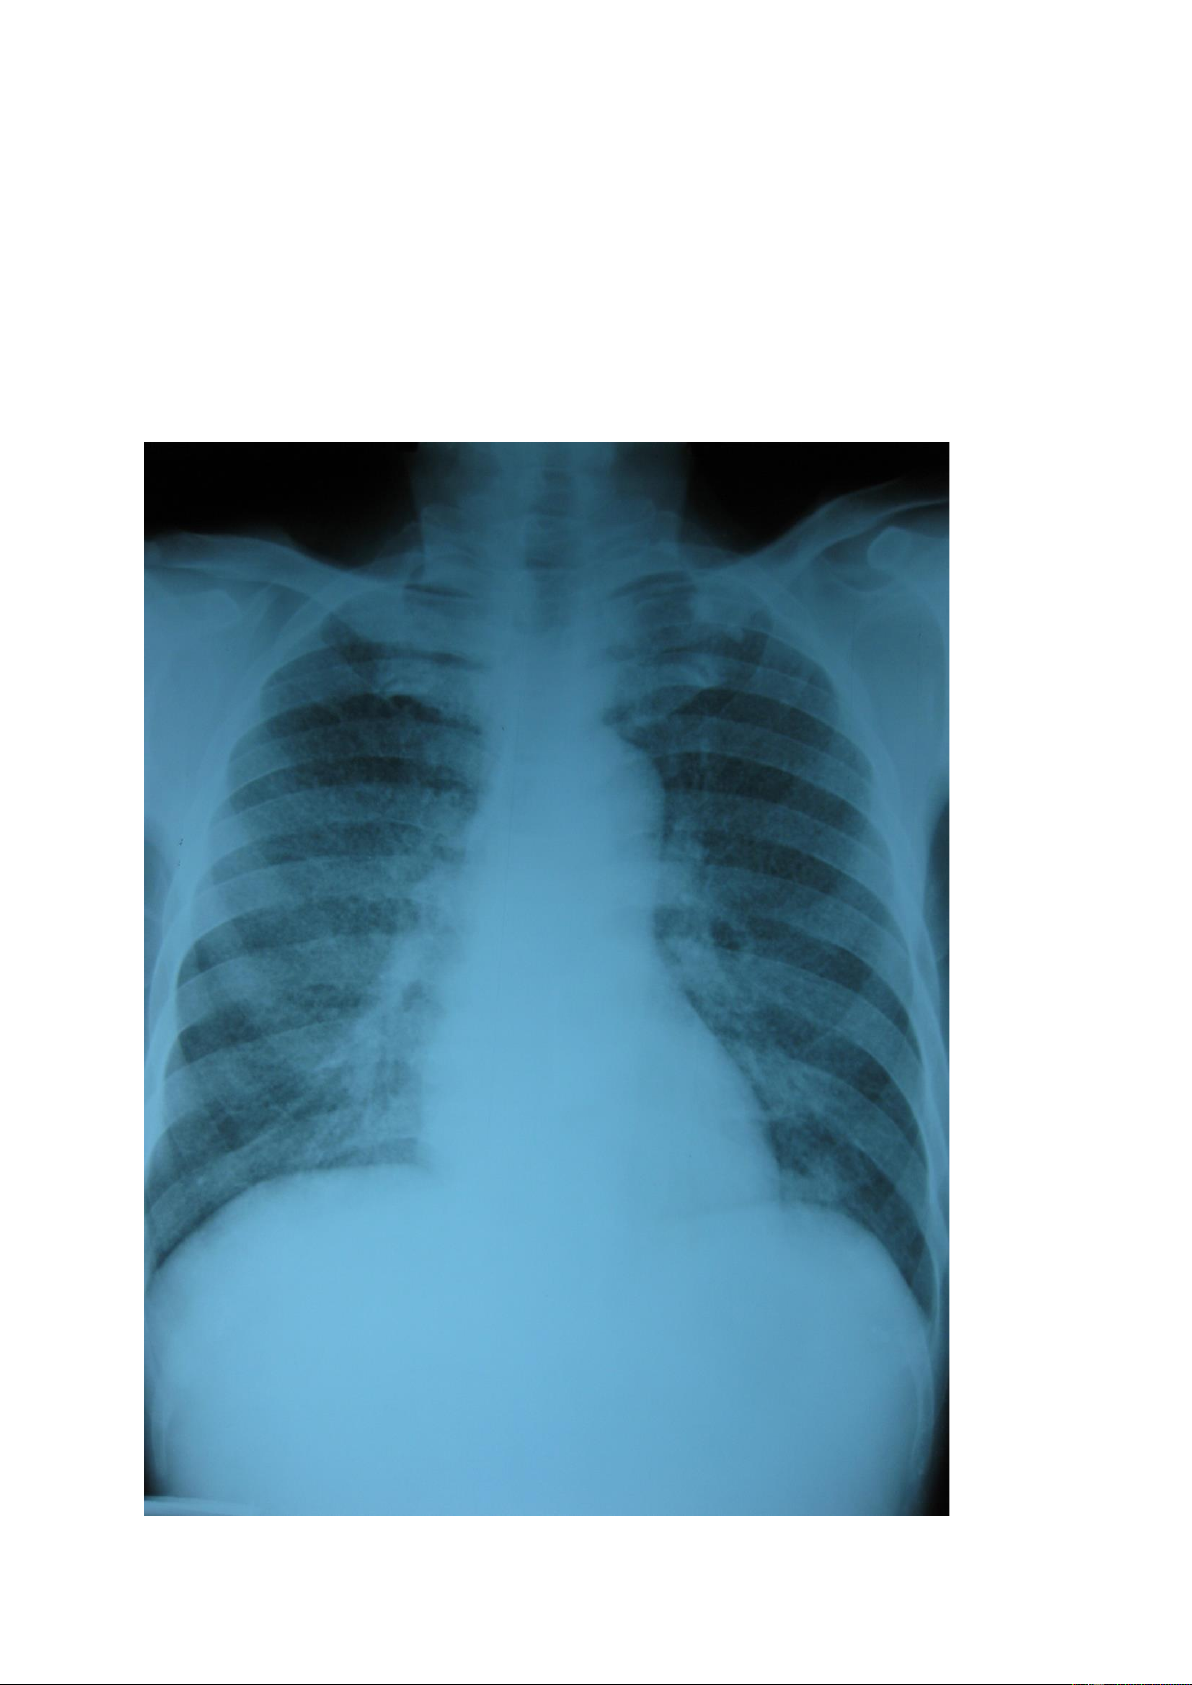

Nốt mờ nhỏ (hạt kê): là tổn thương có kích thước ≤ 3mm, do quan sát bằng

mắt thường nên nếu có số lượng nhiều sẽ thấy các tổn thương có kích thước đều nhau. lOMoAR cPSD| 22014077 1.2.